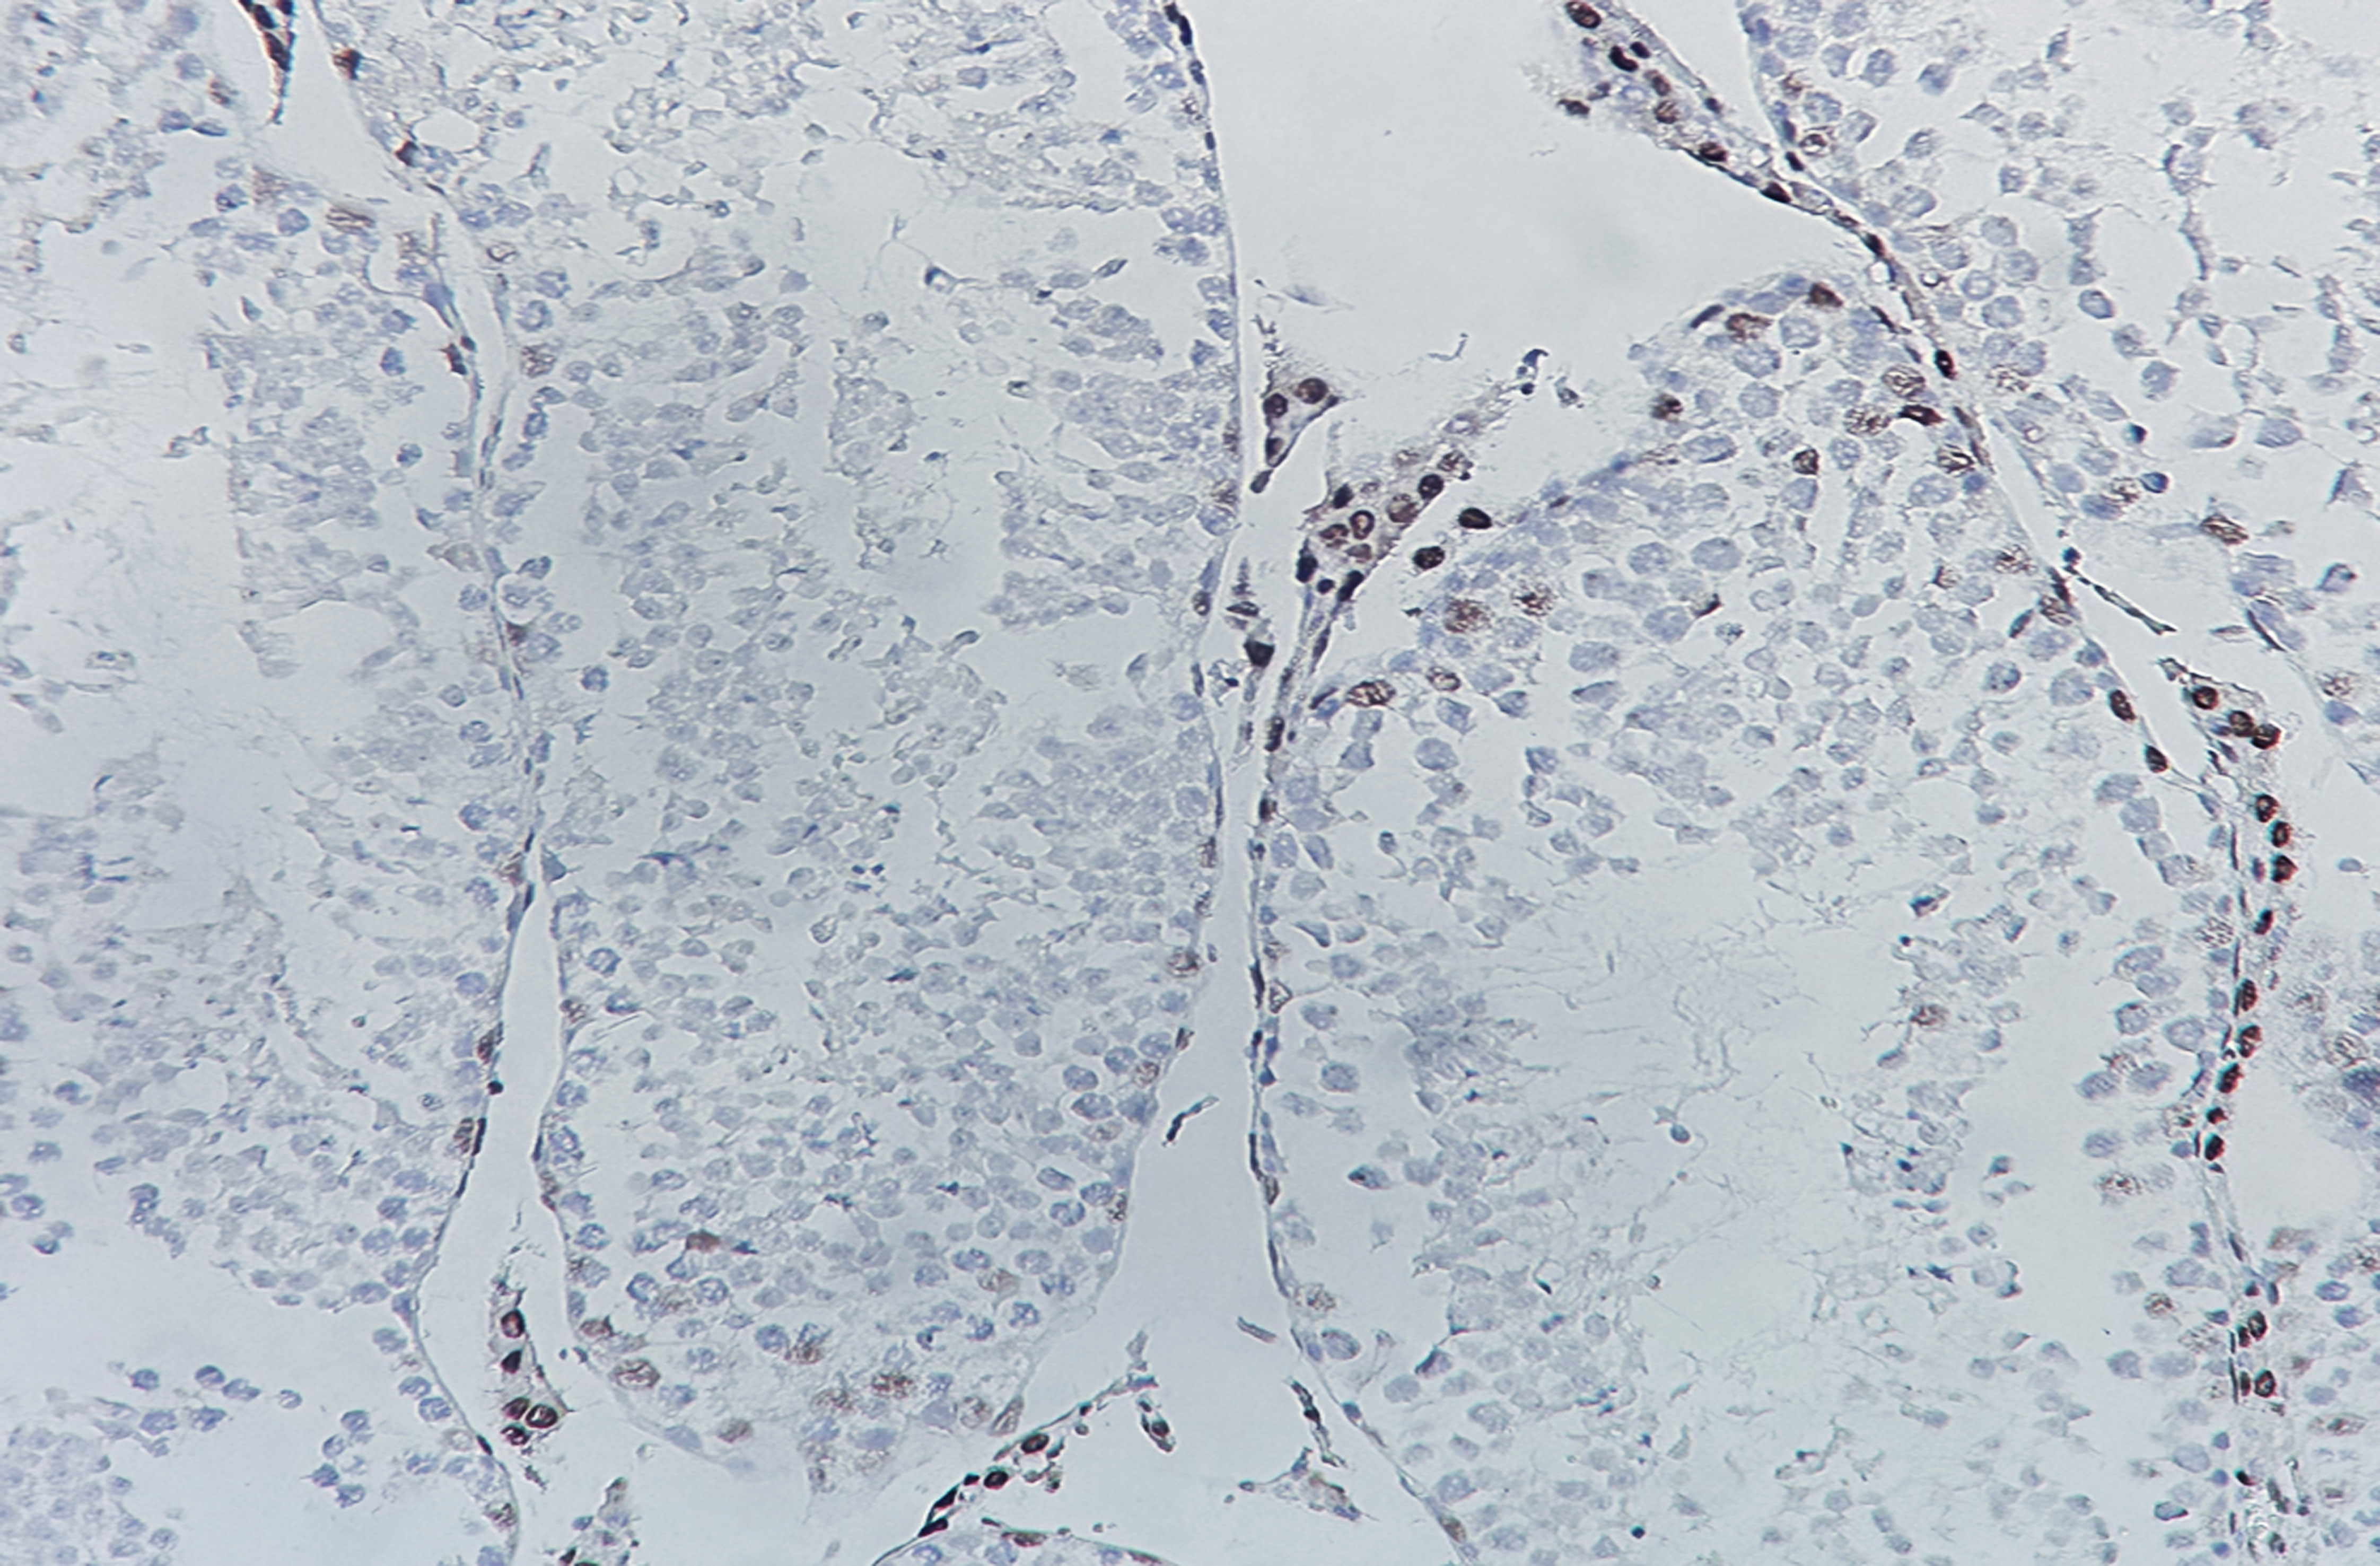

Androgen Receptor (AB1266) mouse mAb

Application:IHC; WB; IF; ELISA

Androgen receptor (AR) is a member of the ligand response transcription regulator superfamily, which is expressed in prostate, testis and sweat gland. Upon AR binding the receptor, it stimulates androgen responsive genes transcription. AR plays an important role in the occurrence and development of prostate cancer. The higher the degree of differentiation of prostate cancer tissue, the higher the expression of AR, and the hormone treatment effect of positive prostate cancer patients is better. AR is mainly used for the detection of prostate cancer, guiding clinical treatment, and can also be used for other cancers such as esophageal cancer and breast cancer.

IHC, 1:200-1:1000 | WB, 1:500-1:2000 | IF, 1:100-1:500 | ELISA, Recommended starting concentration is 1 µg/mL. Please optimize the concentration based on your specific assay requirements.